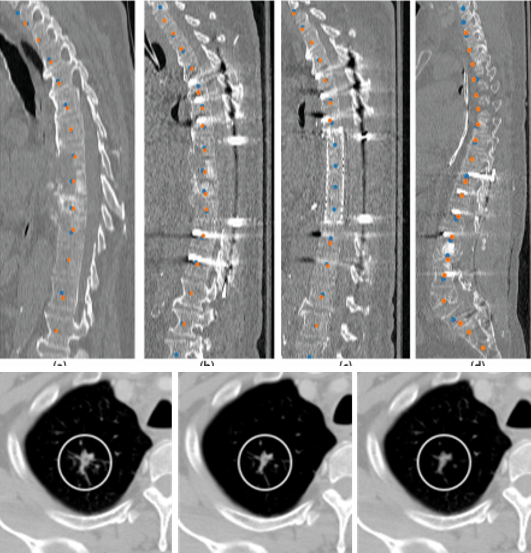

Medical imaging is now used extensively for accurate diagnosis, real-time intervention, and precision medicine. Our work has been focused on fast, high-resolution imaging augmented with functional and metabolic mapping. For example, dynamic 4D MRI under free breathing has been developed using PNCRNNs, with the reconstruction time as fast as 50 bin per second, offering substantial improvement of the image quality for dynamic golden-angle radial imaging of the abdomen. Novel imaging techniques have been developed for high-resolution whole-brain neurometabolic mapping, shedding light on in vivo molecular biomarkers for various brain diseases including stroke, brain tumor, and neurodegenerative disorders. A model-based deep learning architecture, referred to as MoDL-QSM, was developed with improved accuracy for quantifying tissue susceptibility for precise electrode implantation for deep-brain stimulation. To meet the demands for automated identification and localization of the vertebrae, pancreas, colon, lung nodules and other organs in low-dose CT, algorithms integrating local image details and global image patterns have been proposed. To extend the clinical use of nonlinear regression in medical imaging and image analysis, a deep negative correlation learning framework has been proposed to yield a deep regression of ensemble where each base model is both accurate and generalisable.

Vertebrae identification and localization

Chen Y, Gao Y, Li K, Zhao L, and Zhao J. Vertebrae identification and

localization utilizing fully convolutional networks and a hidden Markov model.

IEEE Transactions on Medical Imaging, 2020, 39(2): 387-399.